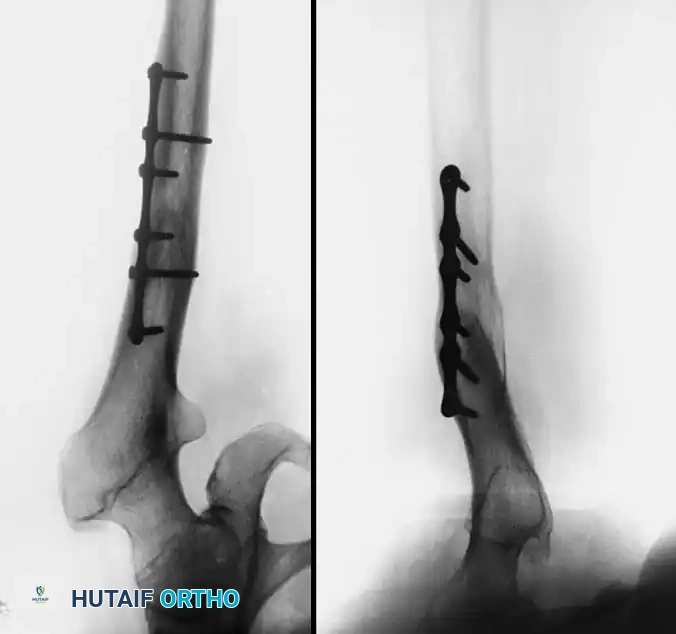

Fig. 7-75 Reconstruction for protrusio acetabuli deformity. A, Diagrammatic representation of medial wall grafting and lateralized cup placement.

Fig. 7-75 Reconstruction for protrusio acetabuli deformity. B, After total hip arthroplasty. Hip center was restored to more lateral and inferior position. Large acetabular component allowed rim fixation without need for screws, and medial deficits were grafted with cancellous autograft from femoral head with excellent incorporation.